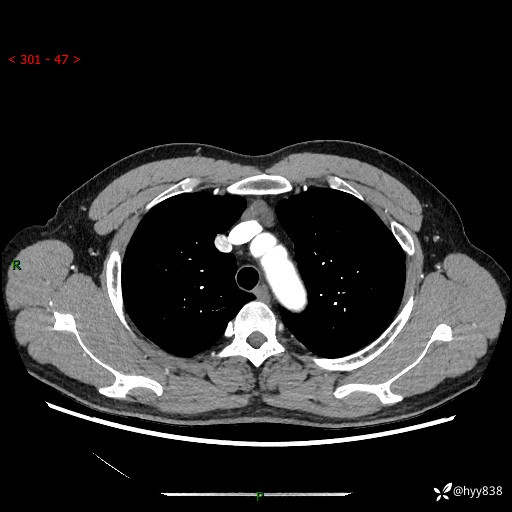

患者性别:女

患者年龄:49岁

简要病史:跟骨骨折,常规CT发现纵隔占位

胸部CT平扫